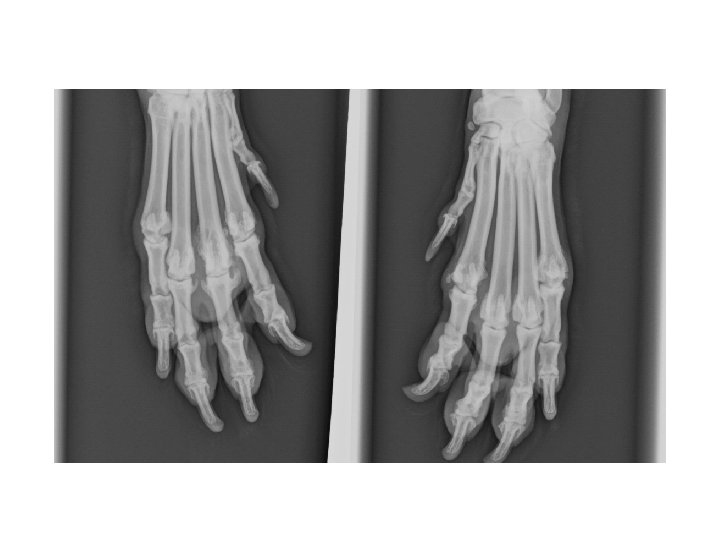

Karpalgelenk